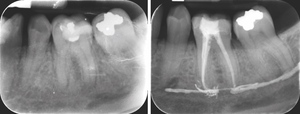

Radiographic examinations consisted of digital orthopantomogram (OPG), peri-apical (PA), and cone beam computed tomography (CBCT) scans. The scans revealed that the lower left first molar root canals were obturated with a radiopaque material, and showed root canal filling extending beyond the apices of the tooth and approximately 5cm along the mandibular canal (Figures 1, 2 and 3).